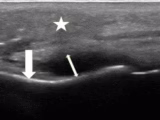

Bilateral Lung Points without Pneumothorax: Exploring “Lung Point” Mimics

Michael Dong, Rebecca Davis, F. Mae West, Gillian Naro, Arthur Au, Jonathan Foster, Jillian Cooper - This study presents a patient case with bilateral lung points in the absence of pneumothorax.